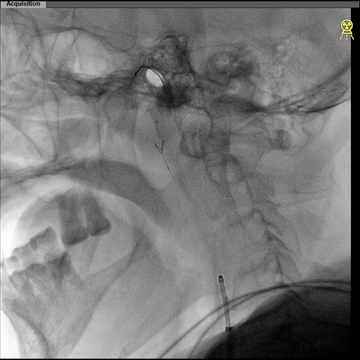

西蒙管于左CCA造影,用硬泥鳅导丝超选入枕动脉,并西蒙管前推上高到枕动脉,加强上支撑,后长鞘顺利过弓,抵达左CCA远端。

建立治疗通路后,保护伞下(NAV6 4-7mm)行左侧ICA起始部狭窄支架植入(wallstent 9*40mm)。